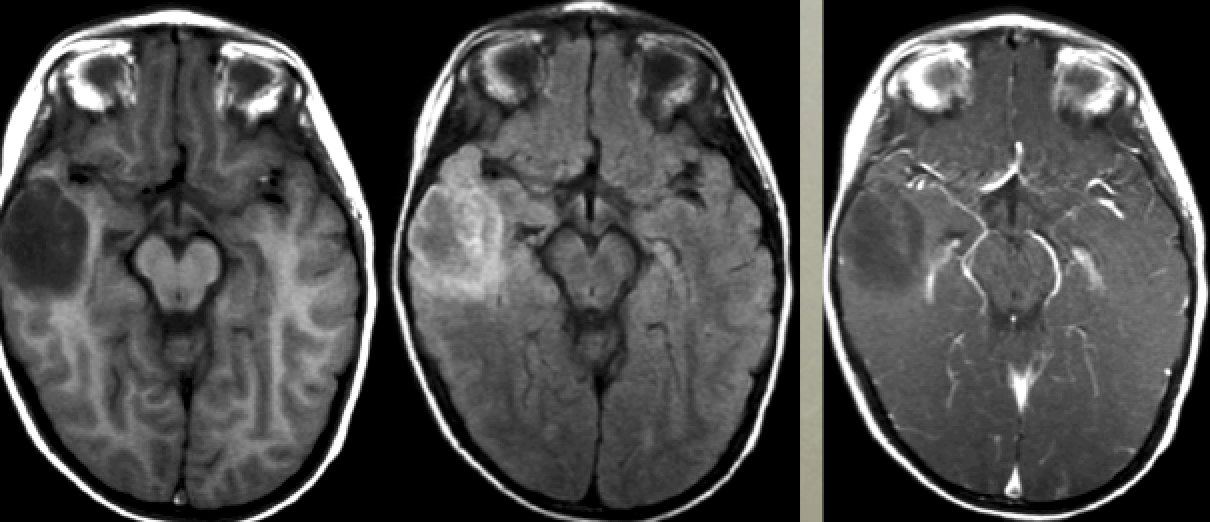

Child with complex partial seizures

Dysembryoplastic Neuroepithelial Tumor (DNET)

Non-enhancing T2 bright, T1 hypodense temporal lobe mass

25 yo with neck stiffness and headache

Ruptured dermoid cyst

Fat in the ventricles is pathognomic

Chemical meningitis

20-30yo dermoid; 40-50yo epidermoid

CPA mass

Diagnosis?

Hint: Pay careful attention to the density/intensity pattern

CPA Lipoma

Hypodense on CT (fat attenuation)

Hyperintense on T1